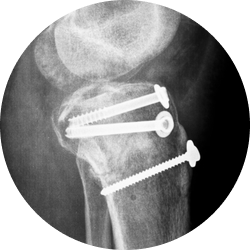

Остеосинтез проводится в отделении травматологии после подготовки. Время процедуры составляет примерно 30–60 минут. Манипуляция выполняется под общим обезболиванием и не причиняет болевых и неприятных ощущений.

Врач выполняет разрез кожи и мягких тканей, визуализируя зону перелома костей.

Руками специалист совмещает костные отломки (репозиция), придавая им правильное анатомическое положение.

Доктор проводит сквозь всю толщу надколенника спицы Киршнера и затем закрепляет их проволокой.

Хирург осматривает область хирургического вмешательства, проводит гемостаз, ставит при необходимости дренаж.

Рана ушивается послойно, закрывается гипсовой повязкой или ортезом.